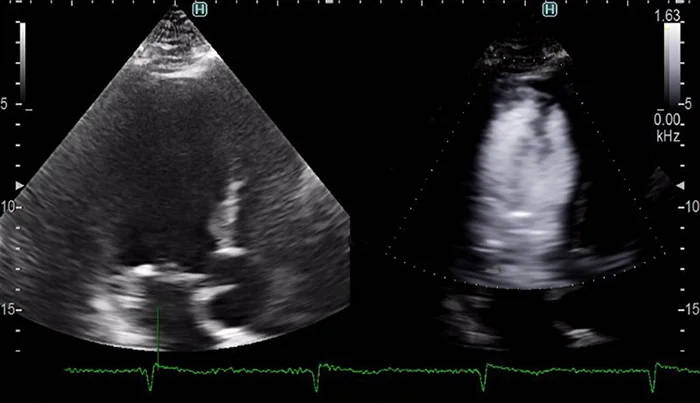

Объёмная эхокардиография

Трёхмерная реконструкция в эхокардиографии обеспечивает более наглядное и точное отображение морфологии сердца. Такое сканирование позволяет не только досконально оценить патологию, но также предоставляет критическую информацию, необходимую для планирования, проведения и оценки эффекта лечения.

Специальная программа производит трёхмерную реконструкцию потоков крови в камере сердца. К примеру, благодаря этому, возможно оценить истинный размер потока регургитации во всём объёме области интереса.

С помощью кардиологического матричного датчика осуществляется одновременный вывод двух плоскостей сканирования в реальном времени, в том числе с цветовым допплеровским картированием кровотока. Доступны поворот или наклон плоскостей друг относительно друга. Такая функция значительно ускоряет процедуру исследования и повышает его наглядность.